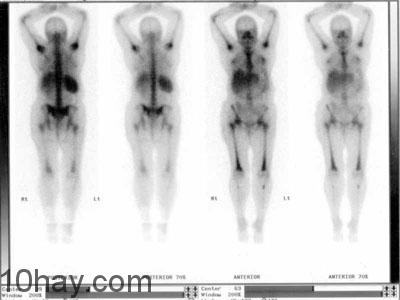

9. Kỹ thuật xạ hình

Máy xạ hình SPECT (Single Photon Emission Computed Tomography) là một trong những thiết bị chẩn đoán hình ảnh hiện đại ngày nay. Về nguyên lý tạo ảnh, SPECT cũng giống như CT (Kỹ thuật SPECT phát triển trên cơ sở CT- Scanner), chỉ khác ở chỗ, với CT thì chùm pho-ton được tạo ra bên ngoài, xuyên qua cơ thể và được ghi nhận ở detector phía đối diện nguồn tia X. Cùng với SPECT, chùm bức xạ photon được phát ra từ bên trong cơ thể do phát ra đồng vị phóng xạ được đưa (uống, tiêm..) vào nơi cần chụp ảnh và chùm bức xạ phát ra được ghi nhận đồng thời bởi hệ detector quay quanh bệnh nhân. Các dược chất phóng xạ được sử dụng với một lượng nhỏ sẽ tập trung về các cơ quan cần ghi hình tuân theo các đặc điểm sinh lý và bệnh lý của ảnh thu được cho ta thông tin về chức năng (Functional image) của cơ quan muốn thăm khám.

Phương pháp này giúp phát hiện các thay đổi về bệnh học ở mức độ phân tử trước khi hoàn thành nên sự thay đổi cấu trúc giải phẫu để có thể nhìn thấy được trên hình ảnh CT, MRI… Máy SPECT cho phép hiển thị hình ảnh không gian 3 chiều rõ rệt đánh giá chức năng các bộ phận trong cơ thể, chuyển hóa tế bào. Máy SPECT có thể chụp toàn thân (Whole body), tĩnh (Static), động (Dynamic), 3 Pha, ảnh cắt lớp tomo,…